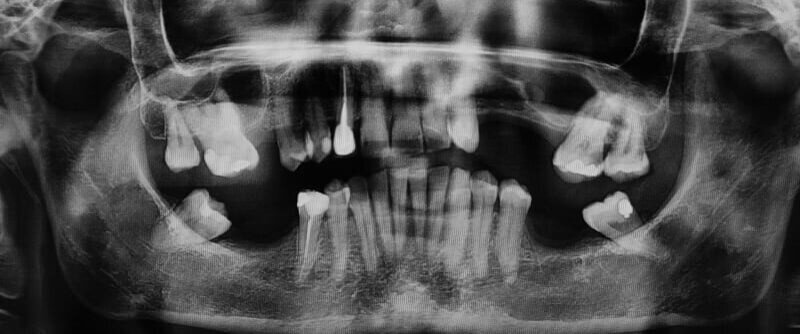

In questo case report è stata selezionata una paziente di sesso femminile, S.P. (54), non fumatrice, con buona igiene orale e con anamnesi negativa all’assunzione di farmaci, ad allergie, disturbi metabolici e patologie sistemiche (Figg. 1-3). È stata proposta una tecnica di rialzo del seno mascellare eseguita mediante strumenti piezoelettrici (Piezosurgery®, Mectron, Genova, Italy) (Figg. 9, 10, 13).

In seguito all’intervento di rialzo di seno mascellare con contestuale GBR è stata eseguita la radiografia ortopanoramica che mostra il corretto riempimento dell’area atrofica del seno mascellare con granuli cortico-spongiosi di osso di origine bovina. Al controllo dopo tre settimane i tessuti molli dell’area trattata risultano perfettamente guariti. La TC Dentalscan effettuata dopo 6 mesi per il controllo della zona rigenerata evidenzia la perfetta guarigione della zona con aumento dello spessore osseo di 5 mm e dell’altezza ossea di 11 mm.